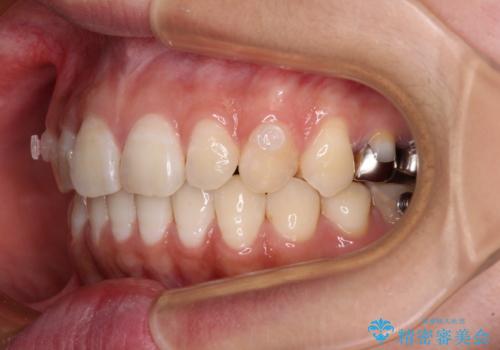

- 下顎の前歯が隠れていることと、デコボコを気にして来院された患者様です。

目立ちにくい装置を希望されていたため、ワイヤー装置とインビザラインを提案したところ、インビザラインを希望されました。

銀歯やムシ歯処置の必要な歯が奥歯にあり気になっていたので、矯正治療の途中でセラミッククラウンへ変更し、その後歯列を仕上げていくこととしました。

咬み合わせと目立っていた銀歯が改善され、患者様には大変満足していただきました。